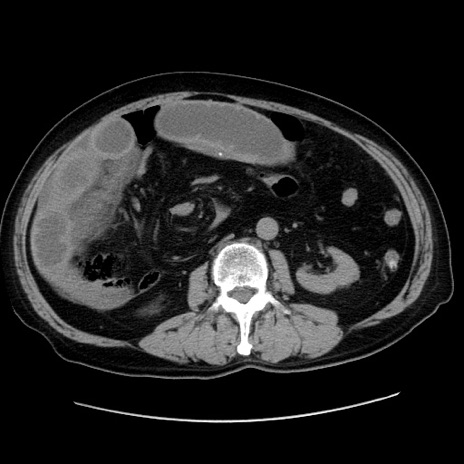

症例30(横断像)

【症例】80歳代男性

【主訴】臍周囲痛

【現病歴】約6時間前から臍下部痛が出現。次第に腹部膨隆・背部痛も生じてきたため来院。背部痛の場所は変化しない。

【身体所見】意識清明、BT 36.3℃、BP  131/87mmHg、P 87bpm、SpO2 100%(RA)、臍周囲自発痛・圧痛あり、反跳痛なし、自発痛部位に一致して板状硬あり、腹部膨隆、腸雑音減弱、CVA tenderness両側陰性。

【データ】WBC 19600、CRP 0.33